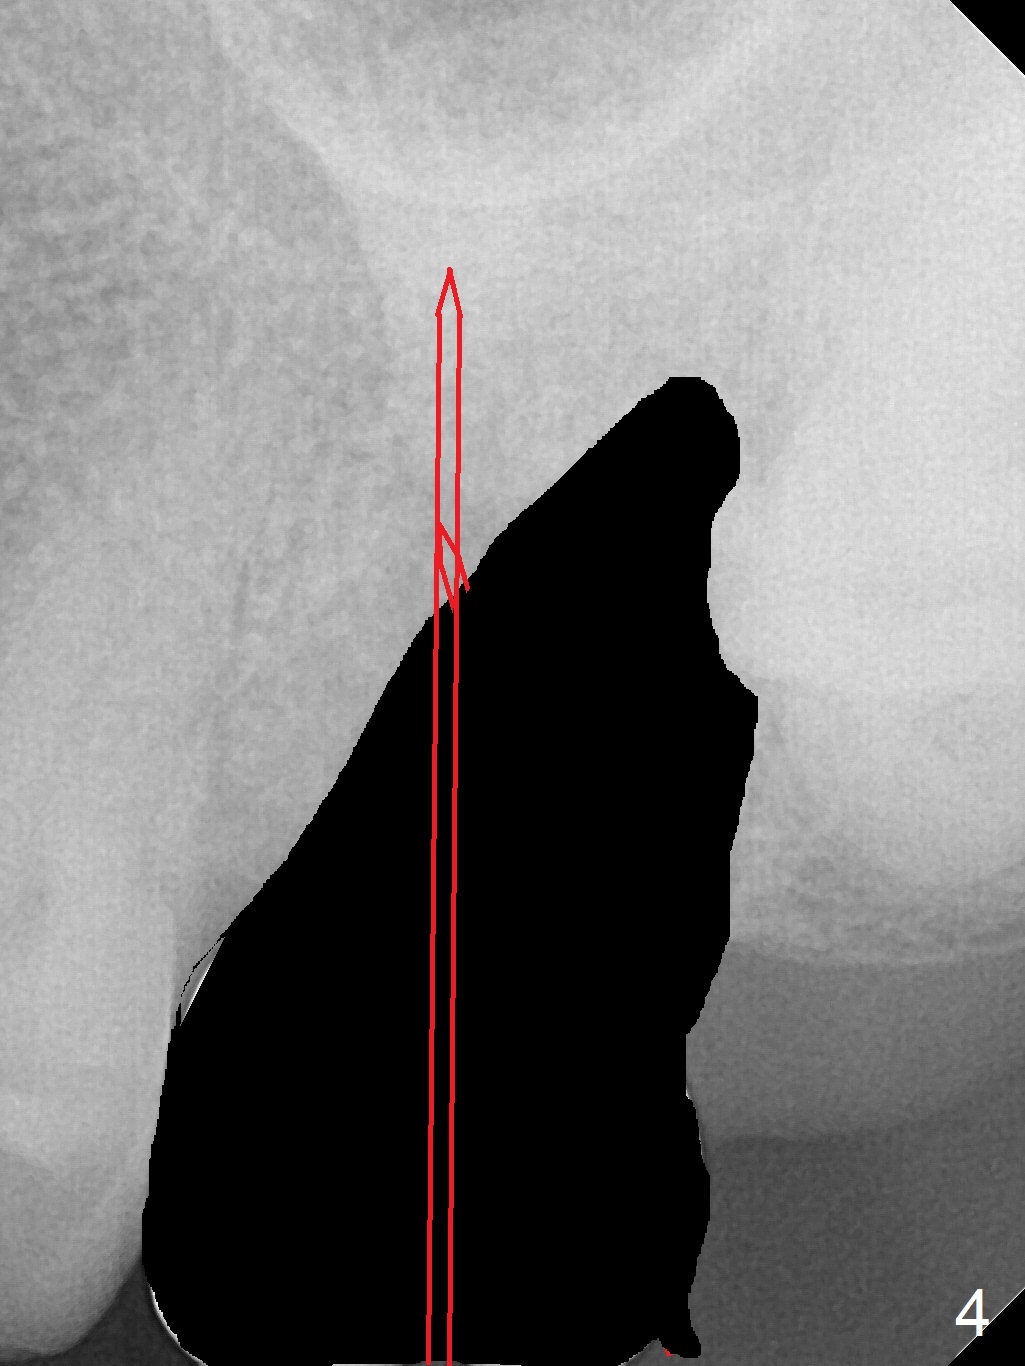

A 64-year-old woman will return for extraction/implant for the upper left 2nd molar with a fistula (Fig.1). Since the roots deviate distal (Fig.2 after extraction), initiate osteotomy in the apical 1/3 of the mesial slope with 1.5 mm drill (Fig.3). Once the lamina dura is penetrated, change trajectory (Fig.4) and extend depth for 15 mm (gingival level). After use of 2 mm drill, insert marked parallel pin for PA. The final implant as well as abutment is shown in Fig.5.